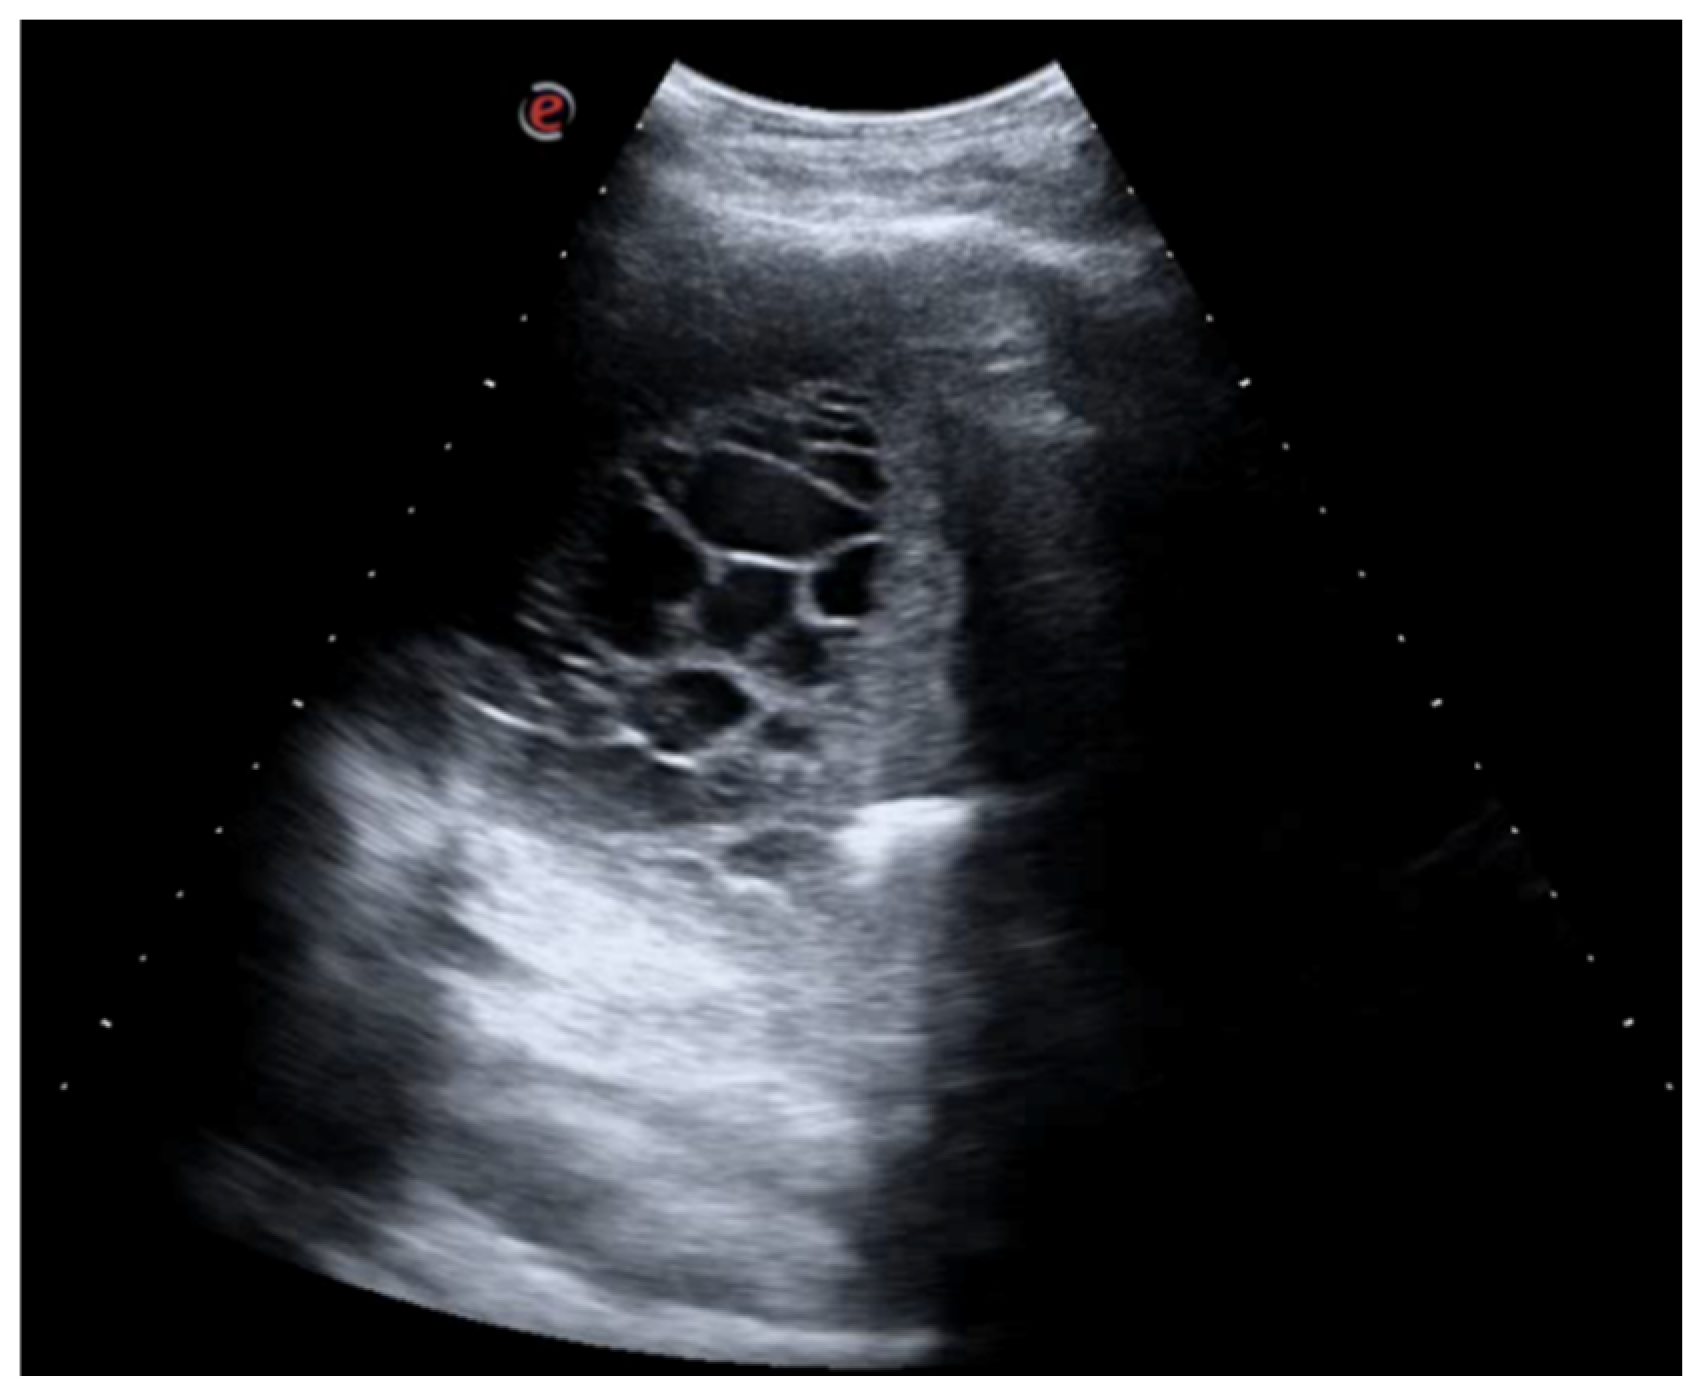

A 60-year-old Caucasian man was admitted to our hospital with a history of worsening pain at the base of the right hemithorax and feeling generally unwell for over one month. The patient’s past medical history included coronary heart disease, with a percutaneous coronary intervention in 2014. He smoked a half-pack of cigarettes per day for 40 years and had no history of respiratory disease. The CT chest scan showed a fluid collection in the medium–lower parts of the right hemithorax with thickened walls and contrast enhancement (Figure 5). This collection appeared in continuity with further smaller fluid collections with thickened walls, contrast enhancement, and confluence and caused the complete atelectasis of the middle and lower lobes and the partial atelectasis of the upper lobe, as well as middle and inferior lobar bronchus occlusion.

Figure 5. Chest CT scan of the mediastinal window in the coronal (A) and axial (B) plane, showing fluid collection in the medium–lower parts of the right hemithorax (maximum axial dimeters of 19 × 13 cm; craniocaudal extension of 16 cm) with thickened walls and contrast enhancement. There is also a complete atelectasis of middle and lower lobes and partial atelectasis of the upper lobe.